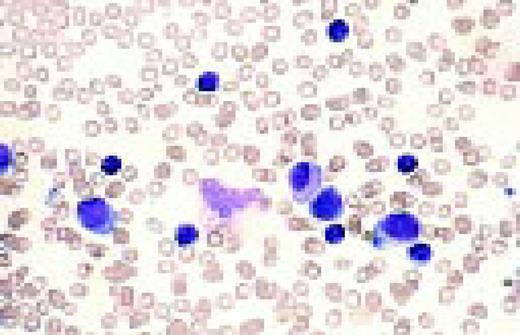

Acute nonlymphoblastic leukemia, FAB classification M5a (L) and M5b (R). The M5a blasts have a moderate amount of cytoplasm and somewhat coarse nuclei. The nucleoli are not unusually prominent. The blasts were positive with the nonspecific esterase stain, and the patient had an associated t(9;11) chromosome abnormality.

The predominant M5b cell is a promonocyte. This cell is characterized by abundant cytoplasm with numerous scattered azurophilic granules and a nucleus with finely dispersed nuclear chromatin. The nuclei are marked by extensive lobulation and creasing. Some of the nuclei have a cerebriform appearance.FIG69